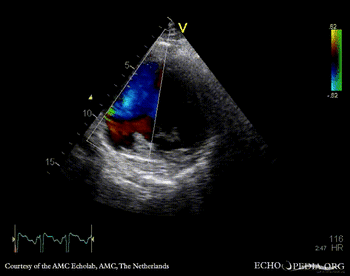

E00831.gif

PSAX with Color Doppler: flow through septal rupture